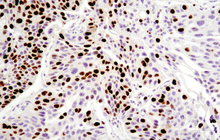

- Immunocytochemistry (ICC) technique

Histological methods includes sample processing in the pathology laboratory, preparation of the slide and its examination under a microscope, sample fixation, molding, microtome cutting, staining and assembly of the slides.